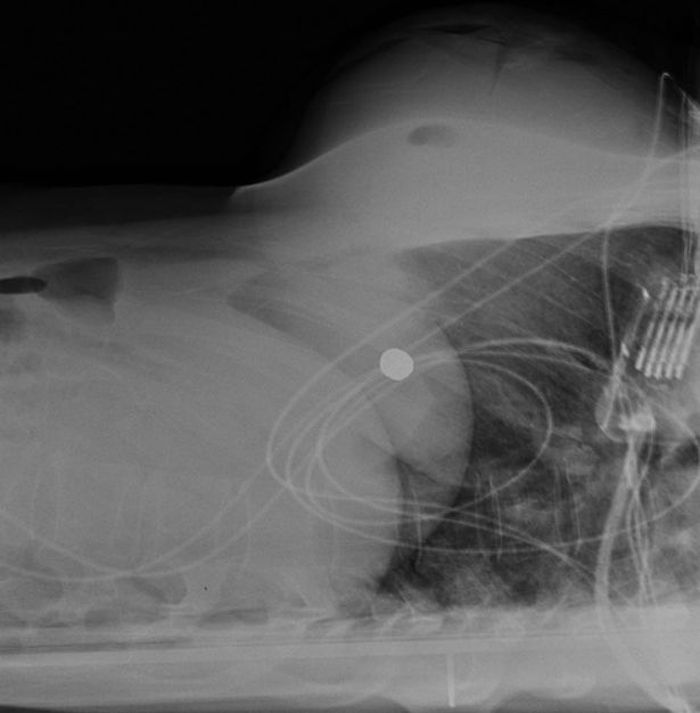

Foto rontgen yang diambil menunjukkan 'peluru kaliber 0,40 berjaket tembaga yang tertanam di implannya.